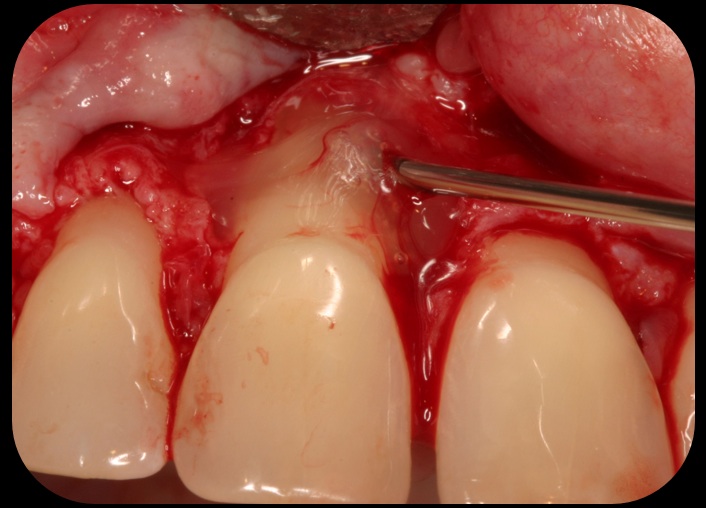

Then, too, are opportunities to prepare the site for regeneration by coupling therapies, applying an enamel matrix derivative, along with traditional bone grafts of demineralized freeze-dried bone allograft; potentially, gains in attachment with minimal probing depth and retained papilla may avoid the need for an implant (Figure 2 through Figure 7).

Severe periodontitis lesion.

Fig. 2

Facial bone loss and a mesial vertical defect.

Fig. 3

Application of enamel matrix derivative.

Fig. 4

Demineralized freeze-dried bone allograft.

Fig. 5

Evidence of clinical attachment gain.

Fig. 6